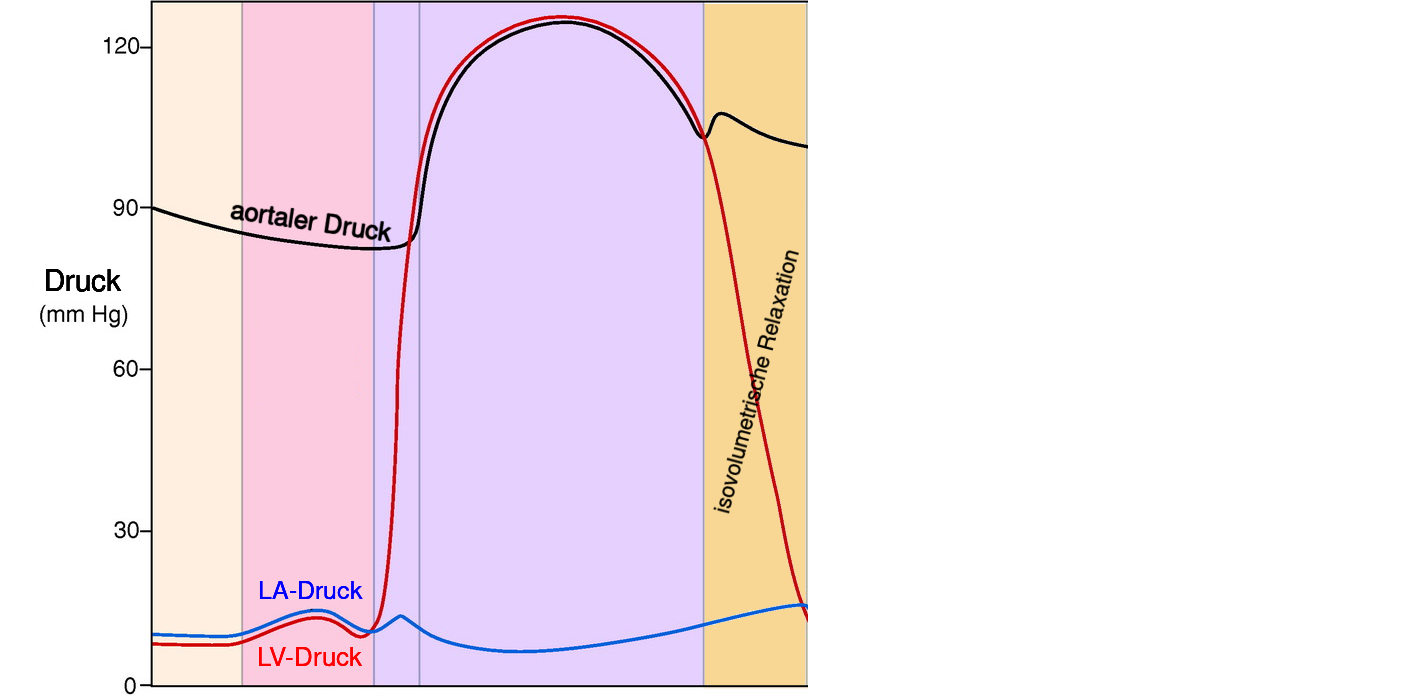

2 Phasen Herzaktion

- der ventrikulären Systole ist die atriale Systole vorgelagert

Vorhofkontraktion (atriale Systole)

- aktive linksventrikulären Füllung

- trägt zu 20 bis 30 Prozent zum gesamten linksventrikulären Füllungsvolumen bei

- erhöht normalerweise den diastolischen Druck hierdurch um weniger als 5 mmHg

die ventrikuläre Systole (kardialer Output)

- durch die Kontraktion hervorgerufene Inwärtsbewegung der Herzmuskelwand steigt der Druck in der Herzkammer —

- wenn der Druck in den Herzkammern den Druck in der Aorta übersteigt, wird Blut ausgeworfen —

die ventrikuläre Diastole (kardialer Input)

- entscheidend für die linksventrikuläre Füllung und damit der Herzfunktion

- für die Füllung muss der LV-Druck kleiner als der LA-Druck sein

- diastolischer LV-Druck wird bestimmt durch intraventrikuläres Blutvolumen, ventrikuläre Dehnbarkeit (Compliance) und durch den von Herzbeutel und rechter Herzkammer auf den linken Ventrikel ausgeübten externen Druck

1. Phase Diastole: isovolumetrische Relaxation

- Zeitraum zwischen Aortenklappenschluss und der Mitralklappenöffnung

- Druck im linken Herzen nimmt bei gleichbleibendem Volumen ab

- rascher Druckabfall

- Aufdrehen (Untwist) und elastische Rückfederung (Recoil) des linken Ventrikels ➙ Saugeffekt ➙ Mitralklappenöffnung und Ventrikelfüllung führt

2. Phase Diastole: auxotonische Relaxation

- Zeitraum zwischen Mitralklappenöffnung und atrialer Kontraktion

- mit Mitralklappenöffnung füllt linker Ventrikel mit variablen Druck

- in späterer Phase Entspannung sämtlicher Herzmuskelzellen

- linke Ventrikel nun nachgiebig, leicht dehnbar und weist normalerweise nur minimalem Widerstand gegenüber Füllung auf